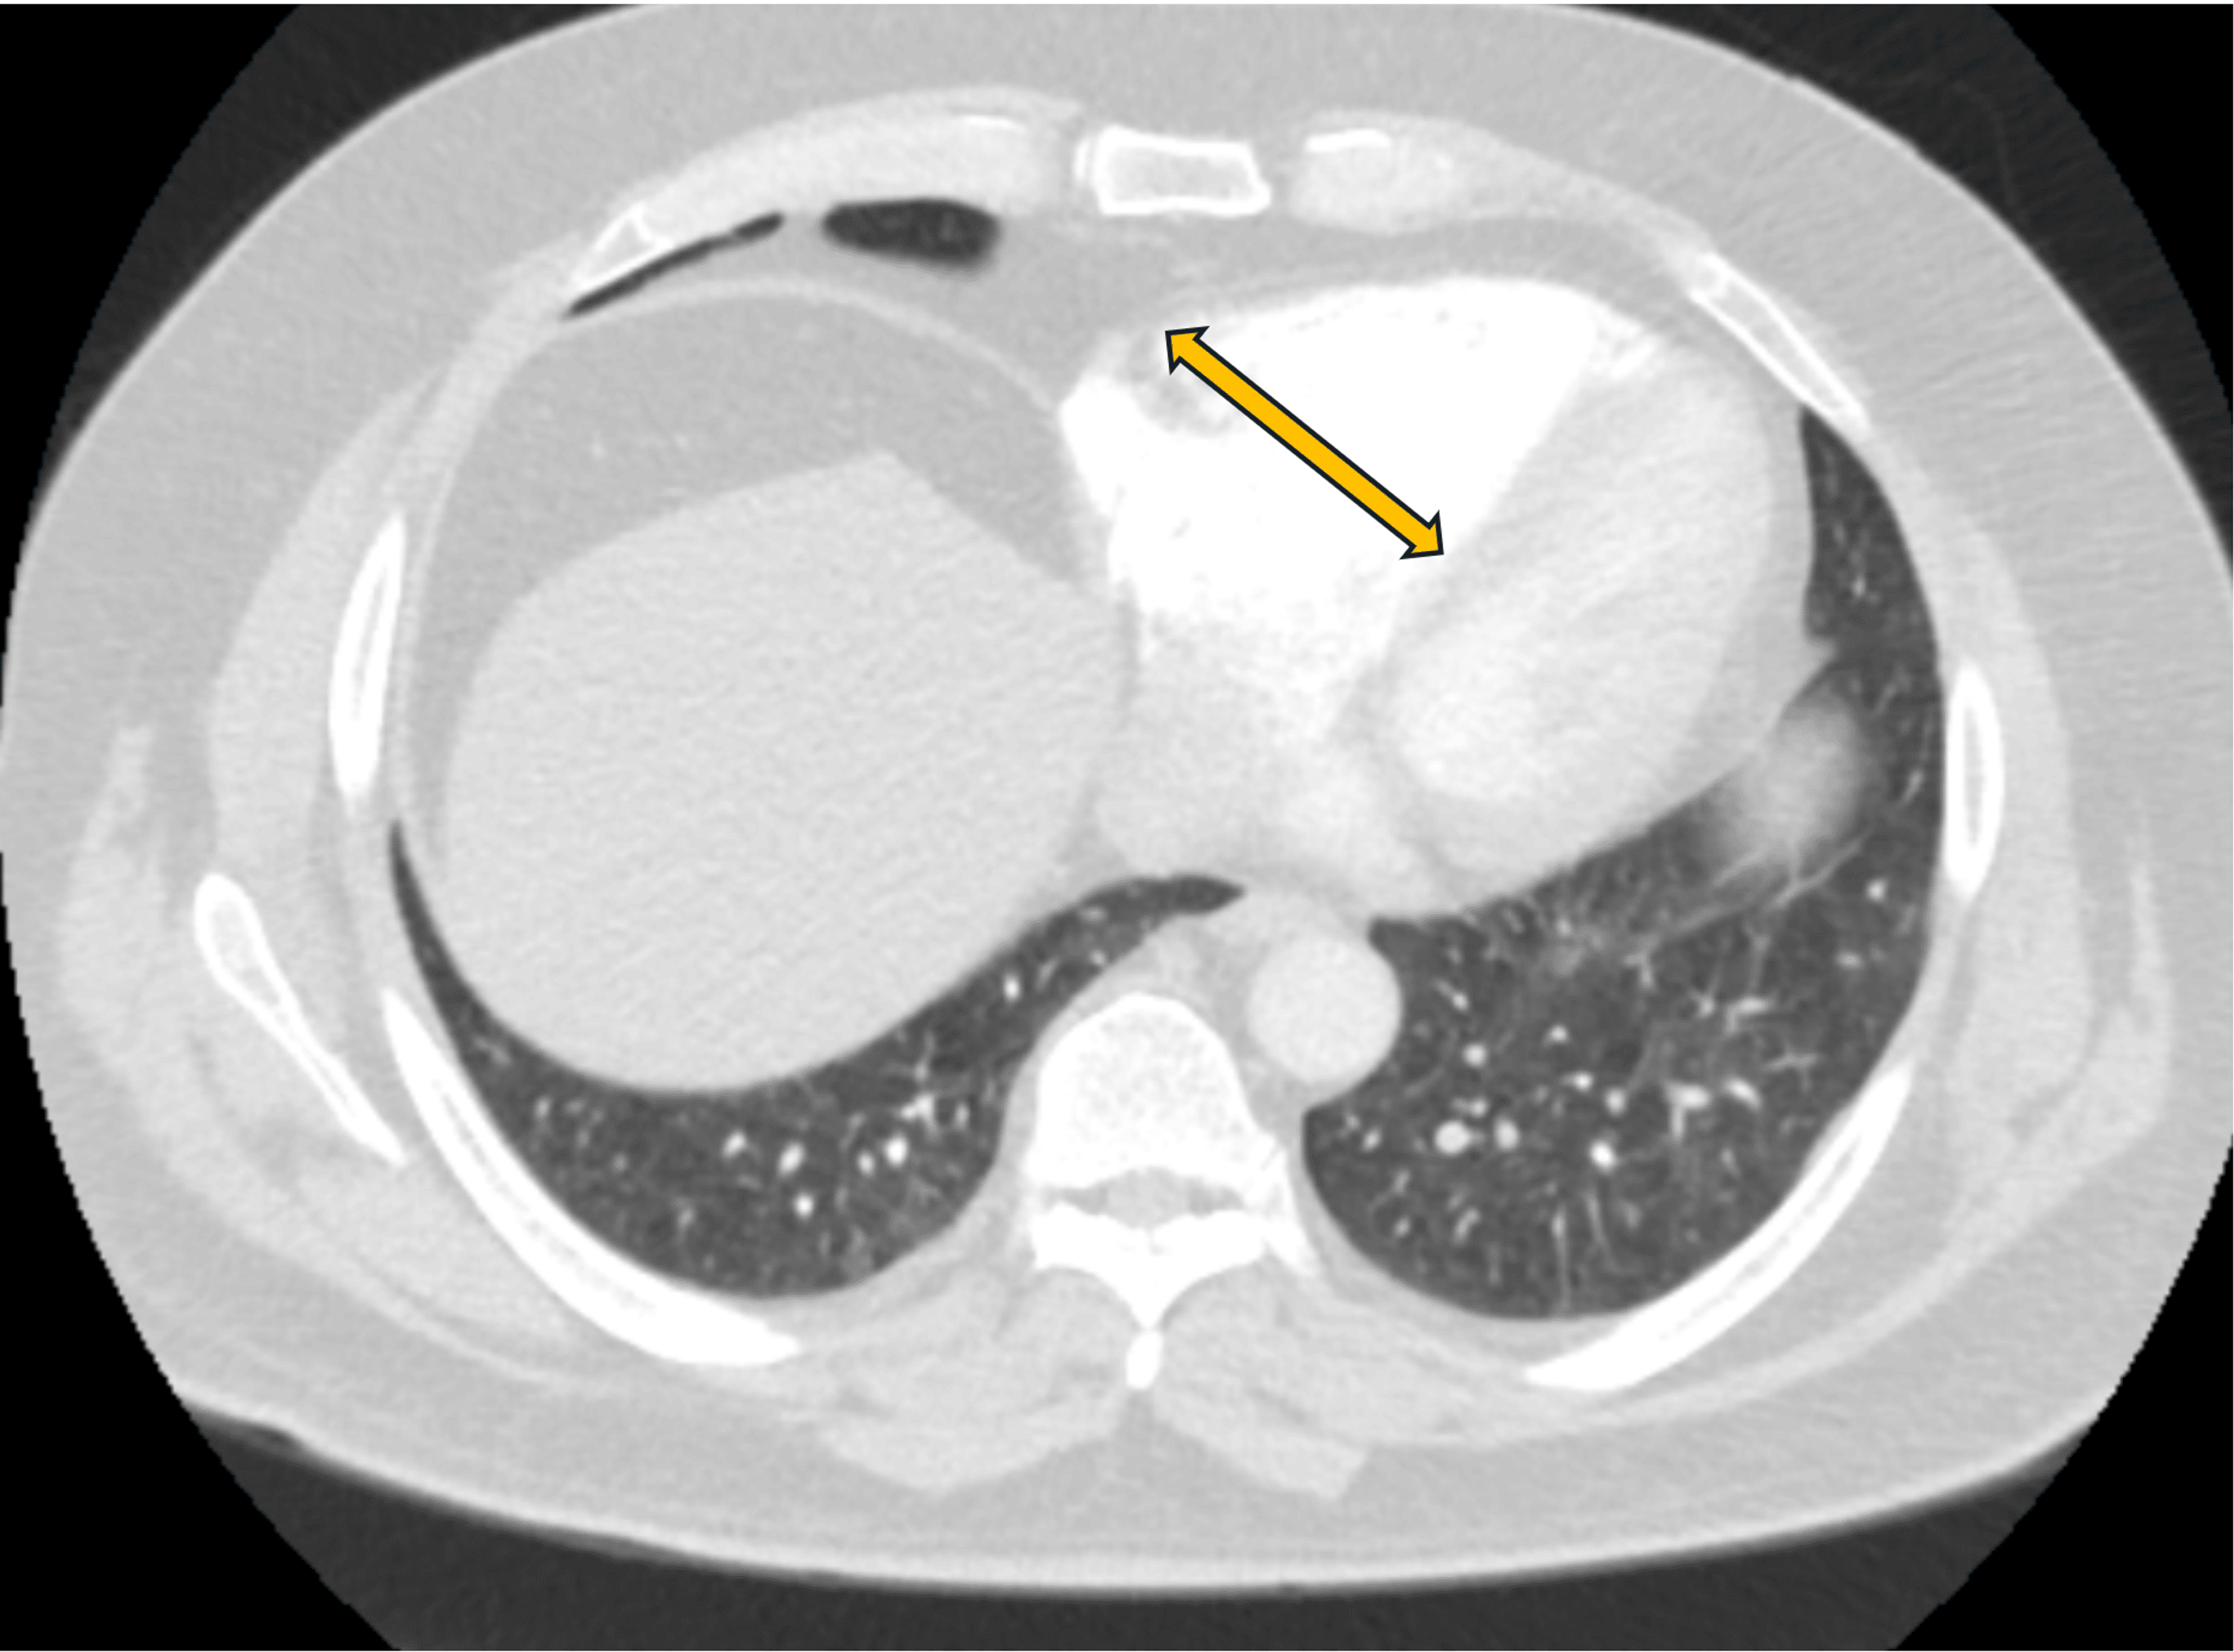

From thrombosisjournal.biomedcentral.com

ProteinC deficiency presenting as pulmonary embolism and myocardial Protein S Deficiency Pulmonary Embolism Protein s deficiency is an inherited thrombophilia associated with an increased risk of thromboembolism. Free and total protein s deficiency was not associated with venous. Conditions such as protein s deficiency, resulting from genetic mutations, are encompassed within this category of causative. Having this deficiency puts you at risk for a blood clot in your leg or arm veins that’s. Protein S Deficiency Pulmonary Embolism.